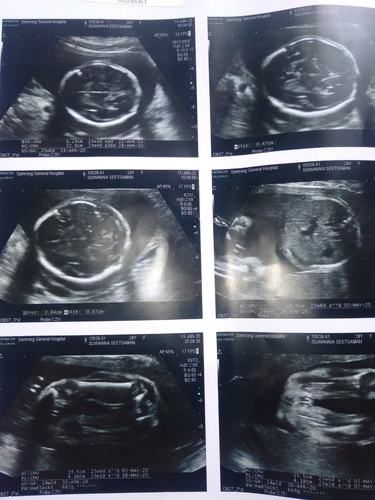

ภาพแรกของหนู 25+2

แม่ๆว่า หญิงหรือชายค่ะ

ภาพนี้ ผญ รึ ชายค่ะ ดูไม่ออกเรย

หญิงค่ะแม่ น้องมีกลีบชัดเจน

ใช่ค่ะ ลูกสาว

หญิงค่ะ ไม่เห็นจู๋